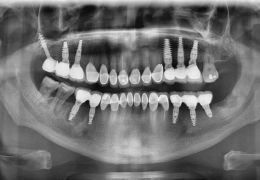

İmplantlar Uygulamaları

Diş implantları ağızda eksik olan dişlerin yerine konması amacıyla, genellikle titanyum veya titanyum bileşiklerinden hazırlanan yapay diş kökleridir.

Titanyum vücut dokuları ile etkileşime girmediği ve kuvvetlere karşı dirençli bir materyal olduğu için implant malzemesi olarak tercih edilir. İmplantlar daha önceden kaybedilmiş dişlerin oluşturduğu boşluklara ya da ciddi bir enfeksiyon yoksa hemen çekim sonrası diş yuvasına yerleştirilebilir.

İmplant uygulamasının asıl amacı, üzerine kullanılabilir dişler yapmaktır.

İmplantlar, sabit ya da hareketli protezler yapmak amacı ile kemiğin yeterli ve uygun olduğu durumlarda basit bir operasyonla çene kemiğine yerleştirilirler. Eğer kemik miktarı ve yoğunluğu istenilen seviyede değilse implant uygulamasından önce kemik oluşturmaya yönelik işlemler yapılması gerekebilir.